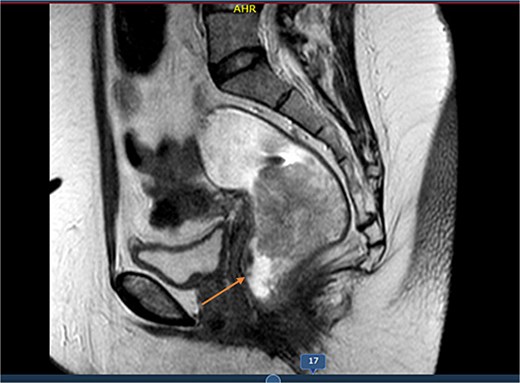

Pelvic magnetic resonance imaging (MRI) revealed a solid, stenosing lesion located 27 mm from the anal verge, extending from the 7 o’clock to 11 o’clock position, infiltrating the muscular layer but without mesorectal fascia invasion. The lesion measured 73 mm longitudinally and 51 mm in both anteroposterior and transverse diameters, located in the mid-to-low rectum, staged as T3N0M0 (Figs 1 and 2).

MRI sagittal view showing the longitudinal extent of the rectal lesion measuring ~73 mm in length, involving the mid-to-distal rectum, consistent with a T3N0M0 tumor staging.